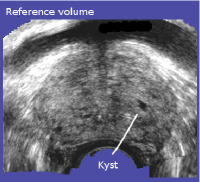

This third study evaluates the accuracy of 687 registrations stemming from 40 patients that were classified as correct. Fiducials were first manually segmented in the panorama volumes, and then in the registered tracking volumes if they were visible. Finding unambiguously identifiable fiducials in the panorama and the majority of the tracking volumes was a challenging task. Segmentation consisted in the definition of the barycenter of a structure. Small structures like calcifications or kysts were preferred since their limited volume facilitates manual barycenter definition and hence reduces the fiducial localization error (FLE), see Fig. 15. We did not segment (parts of) the prostatic capsule since it is difficult to identify anatomically corresponding points on surfaces in US images, i.e. the FLE of the point distance measure would have increased. Surface-distance measures on the other hand underestimate the tissue-correspondence error because they are insensitive to on-surface misalignments. In total, 147 reference fiducials were segmented in the 40 panorama volumes (3.7 fiducials per volume), and 1889 corresponding fiducials were segmented in the 687 tracking volumes (2.7 fiducials per volume). The statistical power of the simple descriptive statistics that were used in this study is ensured by the total number of 1889 evaluated samples, i.e. the small number of samples per registration pair is compensated by the large number of evaluated registrations. The FLE was estimated to 0.35±plus-or-minus\pm0.19 mm via multiple segmentations of the reference fiducials. The anatomical distribution of the reference fiducials is illustrated in Fig. 16. It is important to note that the fiducial segmentations are not used by the registration algorithm; the fiducial registration error is hence a valid estimator of the target registration error (TRE).

Figure 15: Fiducials. Fig. (a) and (b) show corresponding calcifications in the tracking and the panorama volume, Fig. (c) and (d) illustrate a kyst.